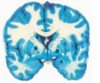

Label the arteries that supply A-C [3]

A

A = anterior cerebral artery (upper

and medial parts of the cortex)

(orange)

B = middle cerebral artery (lateral

areas of the frontal, parietal, and

temporal lobes) (white)

C = posterior cerebral artery (occipital

lobe and inferior parts of the

temporal lobe) (blue)